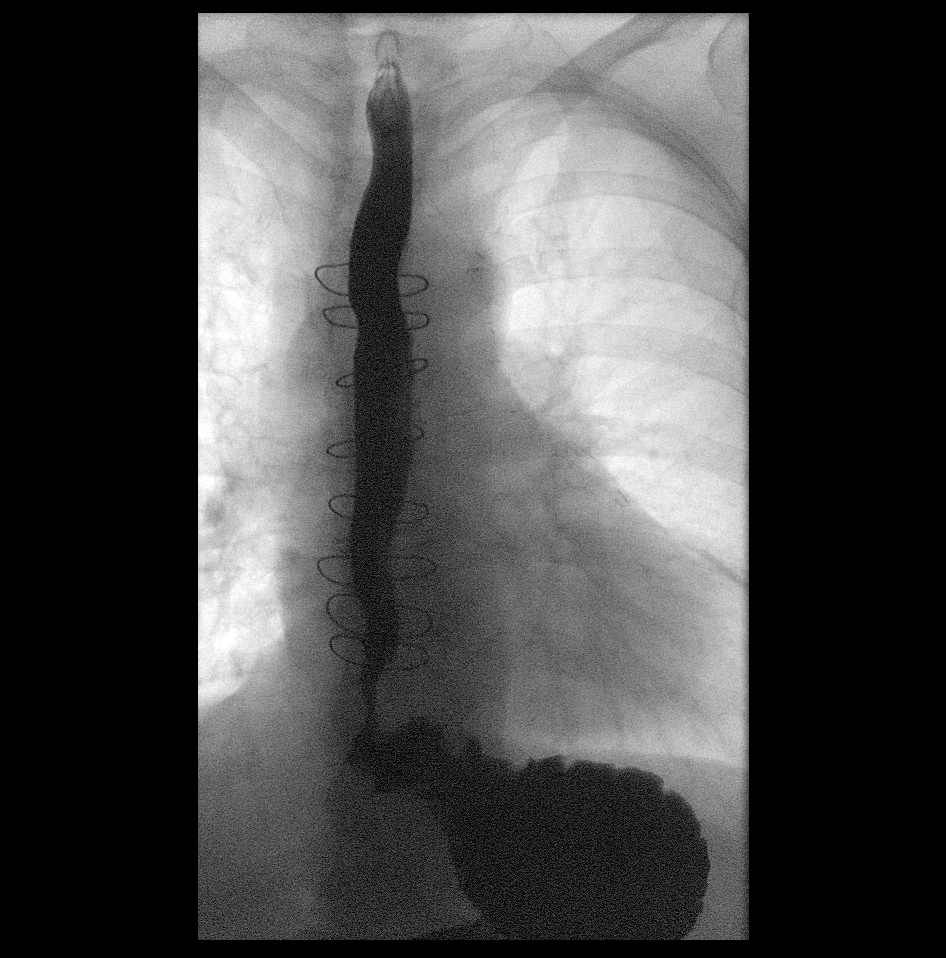

Exhibit C

Shows how the contents of my stomach was flowing into my esohagus.